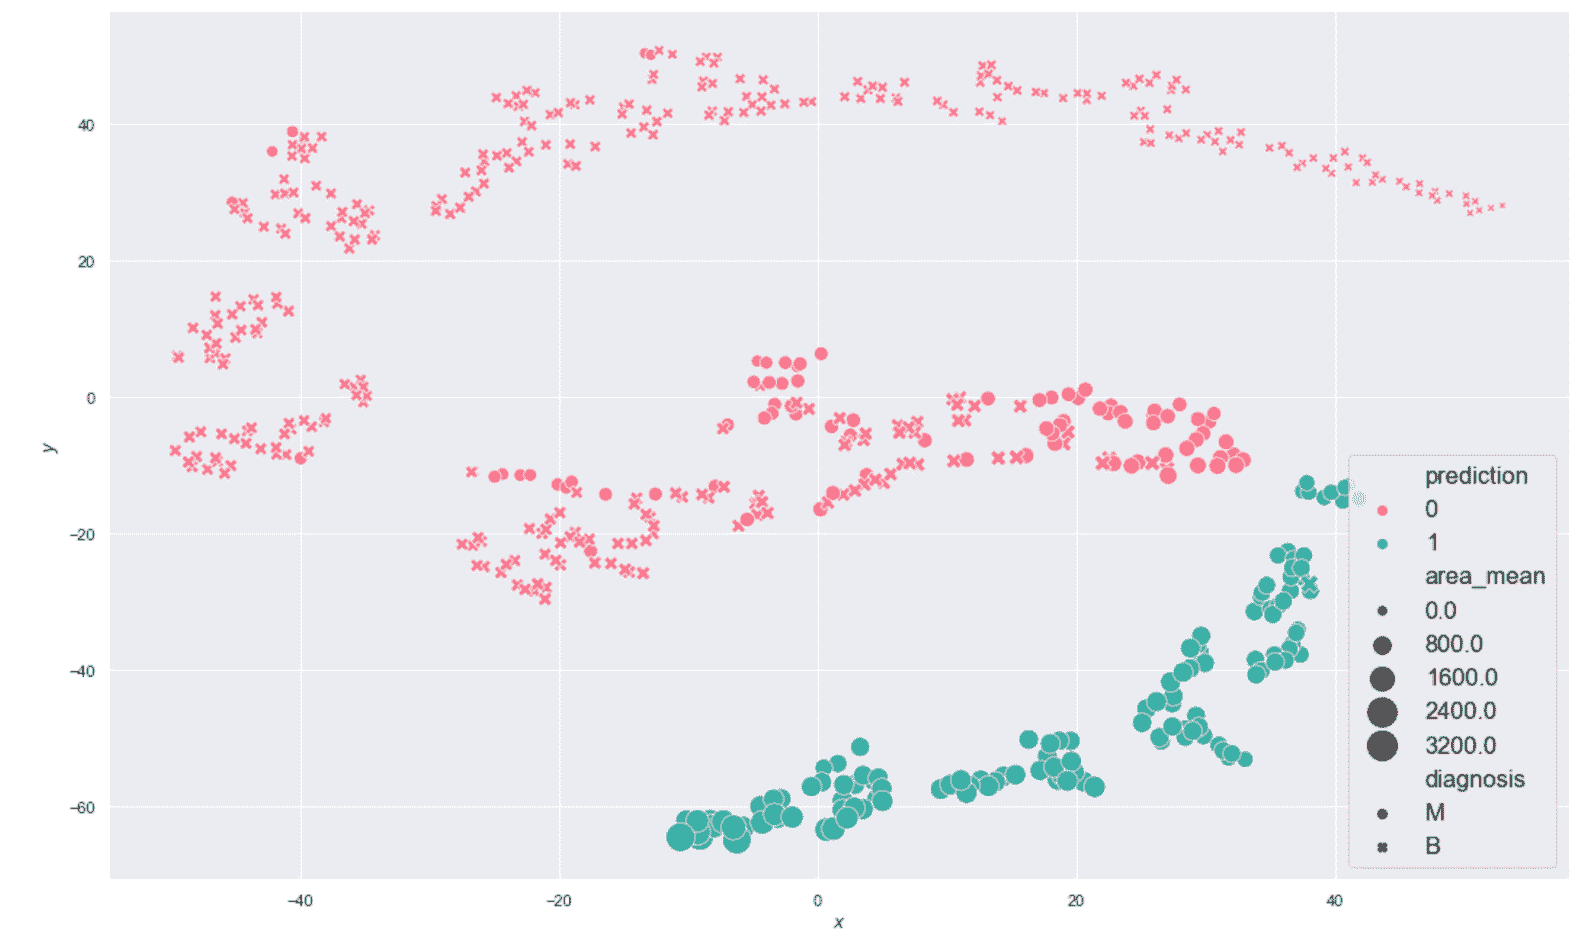

生成的绘图显示在以下屏幕截图中:

乳腺癌威斯康星州数据集的 K 均值聚类(K = 2)

毫不奇怪,该结果对于y < -20相当准确,但该算法无法同时包含边界点(y≈0)进入主要恶性集群。 这主要是由于原始集合的非凸性,并且使用 K 均值很难解决问题。 此外,在投影中,大多数y ≈ 0的恶性样本与良性样本混合在一起,因此,使用基于接近度的其他方法的错误概率也很高。 正确分离这些样本的唯一机会来自原始分布。 实际上,如果可以通过ℜ^30中的不相交球捕获属于同一类别的点,则 K 均值也可以成功。 不幸的是,在这种情况下,混合集看起来非常具有内聚性,因此我们不能指望不进行转换就可以提高性能。 但是,出于我们的目的,此结果使我们可以应用主要评估指标,然后从K > 2移到更大的值。 我们将使用K > 2分析一些聚类,并将它们的结构与配对图进行比较。

生成的绘图显示在以下屏幕截图中:

乳腺癌威斯康星州数据集的 K 均值聚类(K = 8)结果

现在,让我们考虑位于图底部的子群集(-25 < x < 30和-60 < y < -40) , 如下: